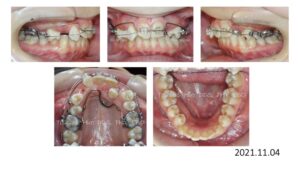

次の症例は叢生です。

50歳の女性です。娘さんがうちで治療した数年後、自分も歯並びを治したいと希望され、治療を開始しました。

上下両側4番抜歯後、上下顎にブラケットを付け、

スペースクローズが終わり、細部の仕上げを行い、

治療期間 2年 7か月で動的治療を終了しました。

人前で笑えるようになりました、と、とても喜んで頂く事が出来ました。